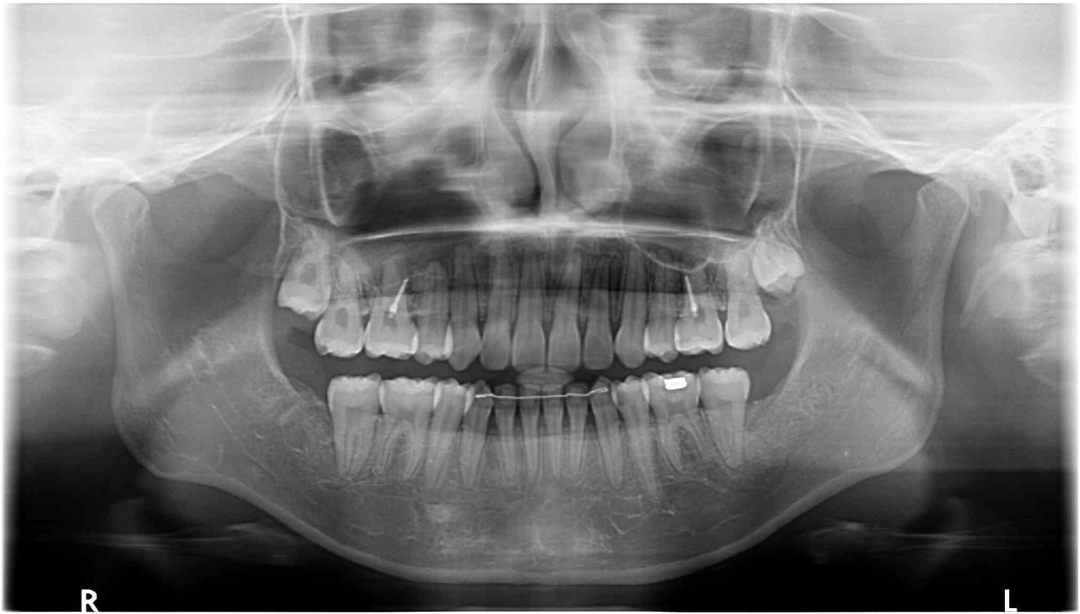

全景片

牙根基本平行,未见牙根吸收